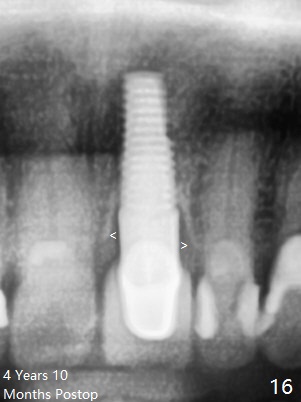

Postop tenderness lasts for two days. The palatal swelling is unnoticeable 7 days postop (Fig.9 *, as compared to A in Fig.8). The bone remains stable around the implant (Fig.10), while the gingiva healthy around the immediate provisional (Fig.11) 5 months postop. Due to insurance limit, the permanent restoration is delayed (16 months postop, Fig.12). The patient is satisfied with the function and appearance 3 years 8 months postop (21 months post cementation, Fig.13,14). PA is taken 4 years 1 month postop (2.5 years post cementation, Fig.15). The lamina dura forms from the most coronal threads (Fig.16). Although there is no bone loss around the implant (Fig.17), metal starts to show 5 years 2 months postop (Fig.18 ^), probably related to the buccal placement, too large the implant for the site or buccal plate atrophy (Fig.19).